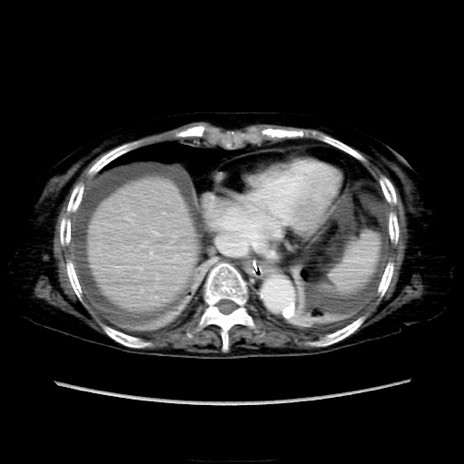

他院CT

横断像